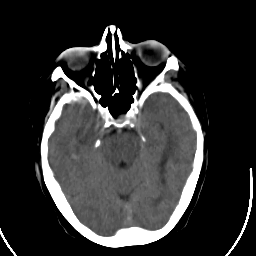

Stroke CT #2 -- Slice #8

[Home][Help][Clinical] Slice 8